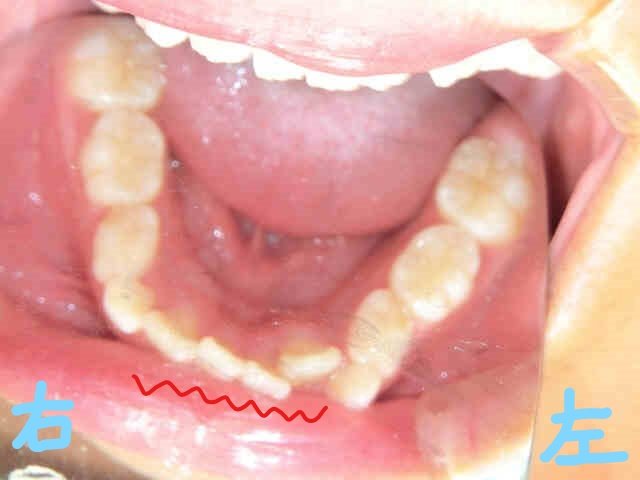

初診時の写真(左上:正面、右上:下から見上げた正面)では、右上前歯(黄色矢印)が内側に入り込み、下顎前歯(赤波線部)には叢生(歯列の重なり=ガタガタの歯並び)が見られました。

さらに上下顎の咬合面の写真からも、上顎前歯の内側移動と、下顎前歯の叢生が確認されます。

このまま成長を迎えた場合、叢生が進行し、犬歯が歯列外に萌出する「八重歯」の状態になる可能性がありました。